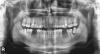

IvanK Опубликовано 20 марта, 2013 Поделиться Опубликовано 20 марта, 2013 Проф.гигиена + обучениеУдаление всех 8-ок + слева внизу 7 ?Консультация пародонтолога, ортопеда, ортодонтаПерелечивание 16,26,37?Имплантация 36,46, 37? Ссылка на комментарий

Dtm Опубликовано 20 марта, 2013 Автор Поделиться Опубликовано 20 марта, 2013 (изменено) Проф.гигиена + обучениеУдаление всех 8-ок + слева внизу 7 ?Консультация пародонтолога, ортопеда, ортодонтаПерелечивание 16,26,37?Имплантация 36,46, 37? Иван спасибо вам за оперативный ответ! Не могли бы вы пояснить немного (прошу прощения за мою некомпетентность, но я не доктор). На данный момент удалены нижние шестерки (точнее то что от них оставалось, были пломбированы лет десять назад) осенью 2012г. Остальные пломбы устанавливались веной-летом 2012г в бюджетной районной поликлинике. Верхние шестерки в процессе лечения (пломба с мышьяком) болели, вплоть до вспышек в глазах с отдачей в ухо (иррадировало в тройничный нерв?). При удалении разделившихся корней правой нижней шестерки на корне висел гнойный мешок (как сказал стоматолог). Кроме того есть рентген пазух и результаты МРТ, в заключении мрт "Выявлено нарушение пневматизации верхнечелюстных пазух и ячеек решетчатого лабиринта за счет неравномерного умеренного утолщения слизистой оболочки / воспалительного генеза/, с наличием экссудативного компонента в гайморовых пазухах ( и горизонтального уровня жидкости с явлением седиментации) занимающего до 1/2 объема пазух. МР картина экссудативного гайморита, этмоидита". Снимок рентген прилагаю (прошу извинить за качество). P.S: Касательно 16 и 26 наверное Вы правы: после лечения между 16 и 15 чернота и она по моему постепенно растет, сам 16 немного кровоточит (можно заметить утром), 26 тоже кровоточит понемногу. А что с 8-ками, левая действительно бывает чувствительна к горячему, за правой не замечал, оба нужно удалять? Изменено 20 марта, 2013 пользователем Dtm Ссылка на комментарий

shishok Опубликовано 20 марта, 2013 Поделиться Опубликовано 20 марта, 2013 Восьмые нижние у Вас никогда не прорежутся из-за неправильного расположения(наклона),если их не удалять,то в последующем проблем будет больше-между 8 и 7 забивается пища(слева уже огромный карман),испортятся и семёрки.Верхние восьмые имеет смысл тоже удалять,т.к.без нижних восьмых они будут смещаться вниз и блокировать движения нижней челюсти,что приведёт к проблемам с ВНЧ суставом. 1 Ссылка на комментарий

Dtm Опубликовано 21 марта, 2013 Автор Поделиться Опубликовано 21 марта, 2013 Восьмые нижние у Вас никогда не прорежутся из-за неправильного расположения(наклона),если их не удалять,то в последующем проблем будет больше-между 8 и 7 забивается пища(слева уже огромный карман),испортятся и семёрки.Верхние восьмые имеет смысл тоже удалять,т.к.без нижних восьмых они будут смещаться вниз и блокировать движения нижней челюсти,что приведёт к проблемам с ВНЧ суставом. Спасибо про 8-ки понял. А можно ли что либо сказать по снимку о вероятности наличия фокальной инфекции? В пазухах жидкость, однако ЛОР в областной больнице заверяла, что гайморита нет, есть мол небольшое искривление перегородки и все. Но после того как у меня весной 2012 заболели верхние 6-ки, появились помутнения в СТ, глаза до сих пор красные, иньекция коньюктивы, блефарит и так целый год уже. Антибиотики что окулисты прописывали ни один не дал сколь либо длительного результата. Одно могу сказать точно - проблемы со зрением появились после того как заболели верхние 6. Есть у меня подозрение, что где то сидит инфекция. Ссылка на комментарий